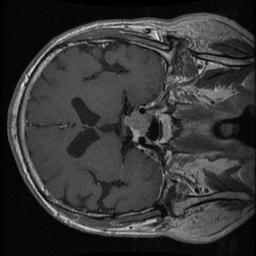

We have further enhanced the experimental setup by incorporating additional photographs to measure the impact of the image preprocessing techniques proposed in this paper. In Figure 6a and 6b, we present a selection of before-and-after images randomly selected from our dataset, illustrating the demonstrable effects of the image processing methods employed. These visual examples serve to provide compelling evidence of the efficacy of our image preprocessing approach, enhancing the attractiveness and visual appeal of our research

Refer to caption

(a) Before Image Preprocessing

(b) After Image Preprocessing

Figure 6: Sample of before and after image preprocessing